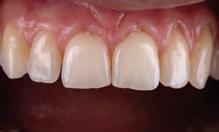

Fig. 5a: The patient was unhappy about the appearance of her smile due to a Bolton discrepancy. Patient desires to have a beautiful smile.

Fig. 5b: Use palatal matrix with the proposed changes transferred from the wax-up.

Fig. 5c: Palatal contours built over the palatal matrix.

Fig. 5d: Post-operative results after restoration.